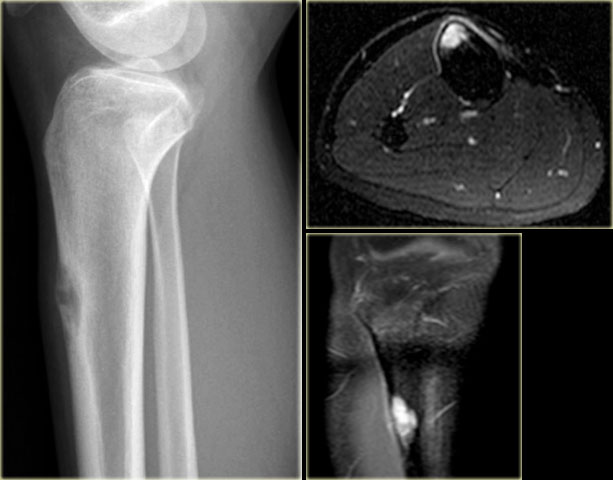

Brown tumor (2)

On the left images of a 30-year-old male with well-defined lytic lesion of the olecranon.

On the radiograph several ridges can be seen and a pathologic fracture (arrow).

The T2-weighted image with fat saturation demonstrates fluid-levels due to sedimentation.

Most likely diagnosis: giant cell tumor and ABC.

Biopsy revealed brown tumor.

Here images of a 33-year old male with a diaphyseal eccentric sharply defined lytic lesion predominantly located in the cortical bone.

CT shows the cortical origin with thin peripheral rim in this patients with hyperparathyroidism.

Diagnosis: Brown tumor.